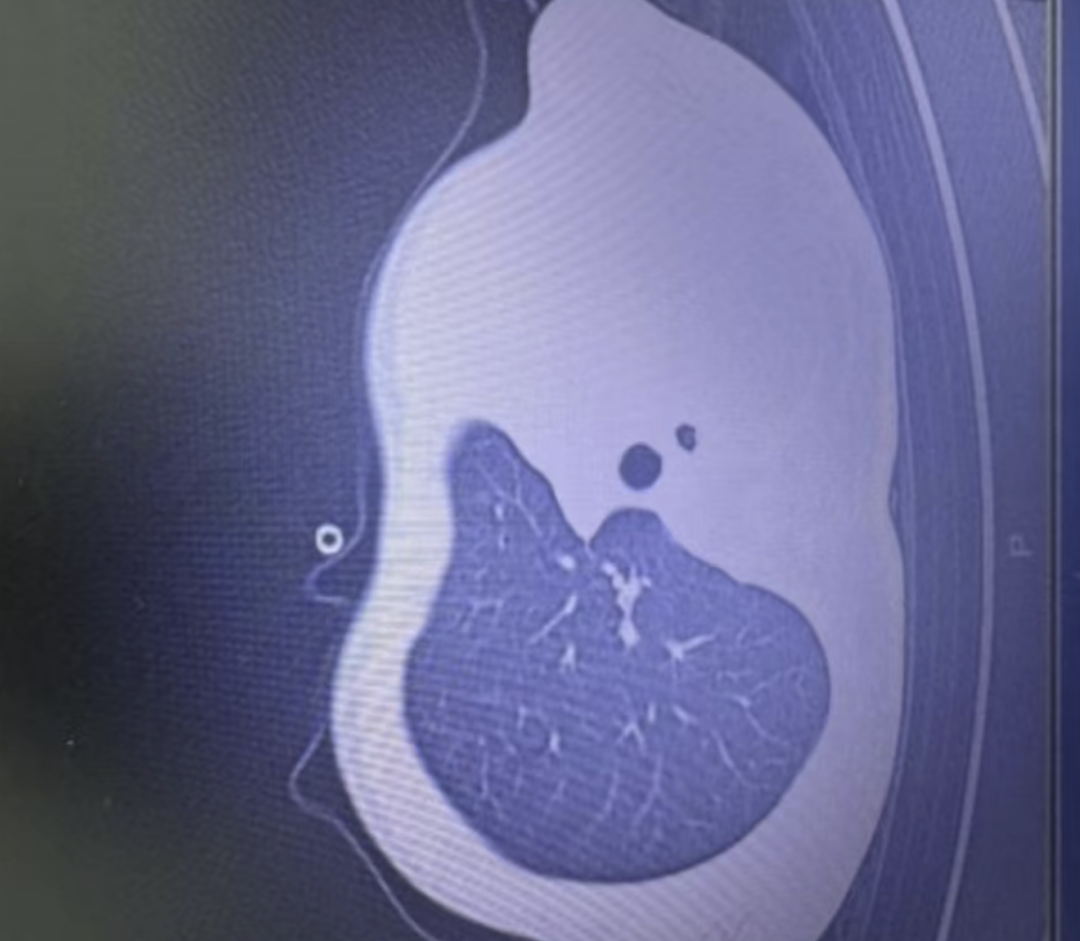

国内今天也爆出一名1岁男童病例,就因为感染流感病毒,短短一天的时间,就从轻微发烧咳嗽直接发展到肺堵死,出现“白肺”缺去鬼门关走了一遭!